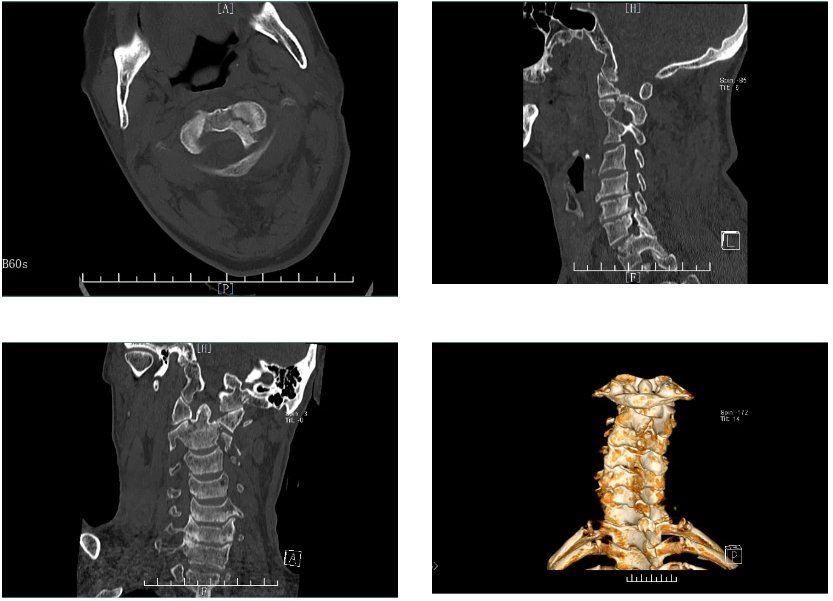

患者 L 大爷,在家里不慎从高处跌落,头部着地,起初无明显不适,直到晚上睡觉时感到颈部疼痛不适,于当地医院检查为第 2 颈椎骨折(又称 Hangman 骨折)。予输液、颈部枕颌带牵引,仍感觉颈部疼痛无好转,于是在家人陪同下前往正兴医院找到了骨科中心康两期主任医师。

经过细致检查和术前讨论,骨科中心康两期主任医师团队为 L 大爷制定了最合适的治疗方案。

在手术室麻醉科医护人员的密切配合下,康两期主任医师团队为患者施行寰枢椎骨折后路切开复位内固定术,术中见枢椎齿状突基底部骨折,骨折端稍移位,予复位及椎弓根钉固定,骨折端位置良好,颈椎高度恢复正常。

历经 2 小时,康两期主任凭借精湛的技术和丰富的经验,顺利完成这例高难度的手术,术中出血极少,术后患者恢复良好,术后影像显示骨折部位已复位,固定可靠。

同期,另外一名患者张阿姨因外伤致颈部酸痛、活动受限,紧急送往我院治疗,CT 示:第一颈椎骨折(又称 Jefferson 骨折)伴寰枢关节脱位,右桡骨远端骨折。

经骨科中心团队综合评估后,由康两期主任医师主刀为患者顺利完成后路颈1、2骨折切开复位椎弓根钉内固定术+右桡骨远端骨折切开复位钢板内固定术,手术顺利,术后患者清醒,安返病房。后续张阿姨恢复良好。